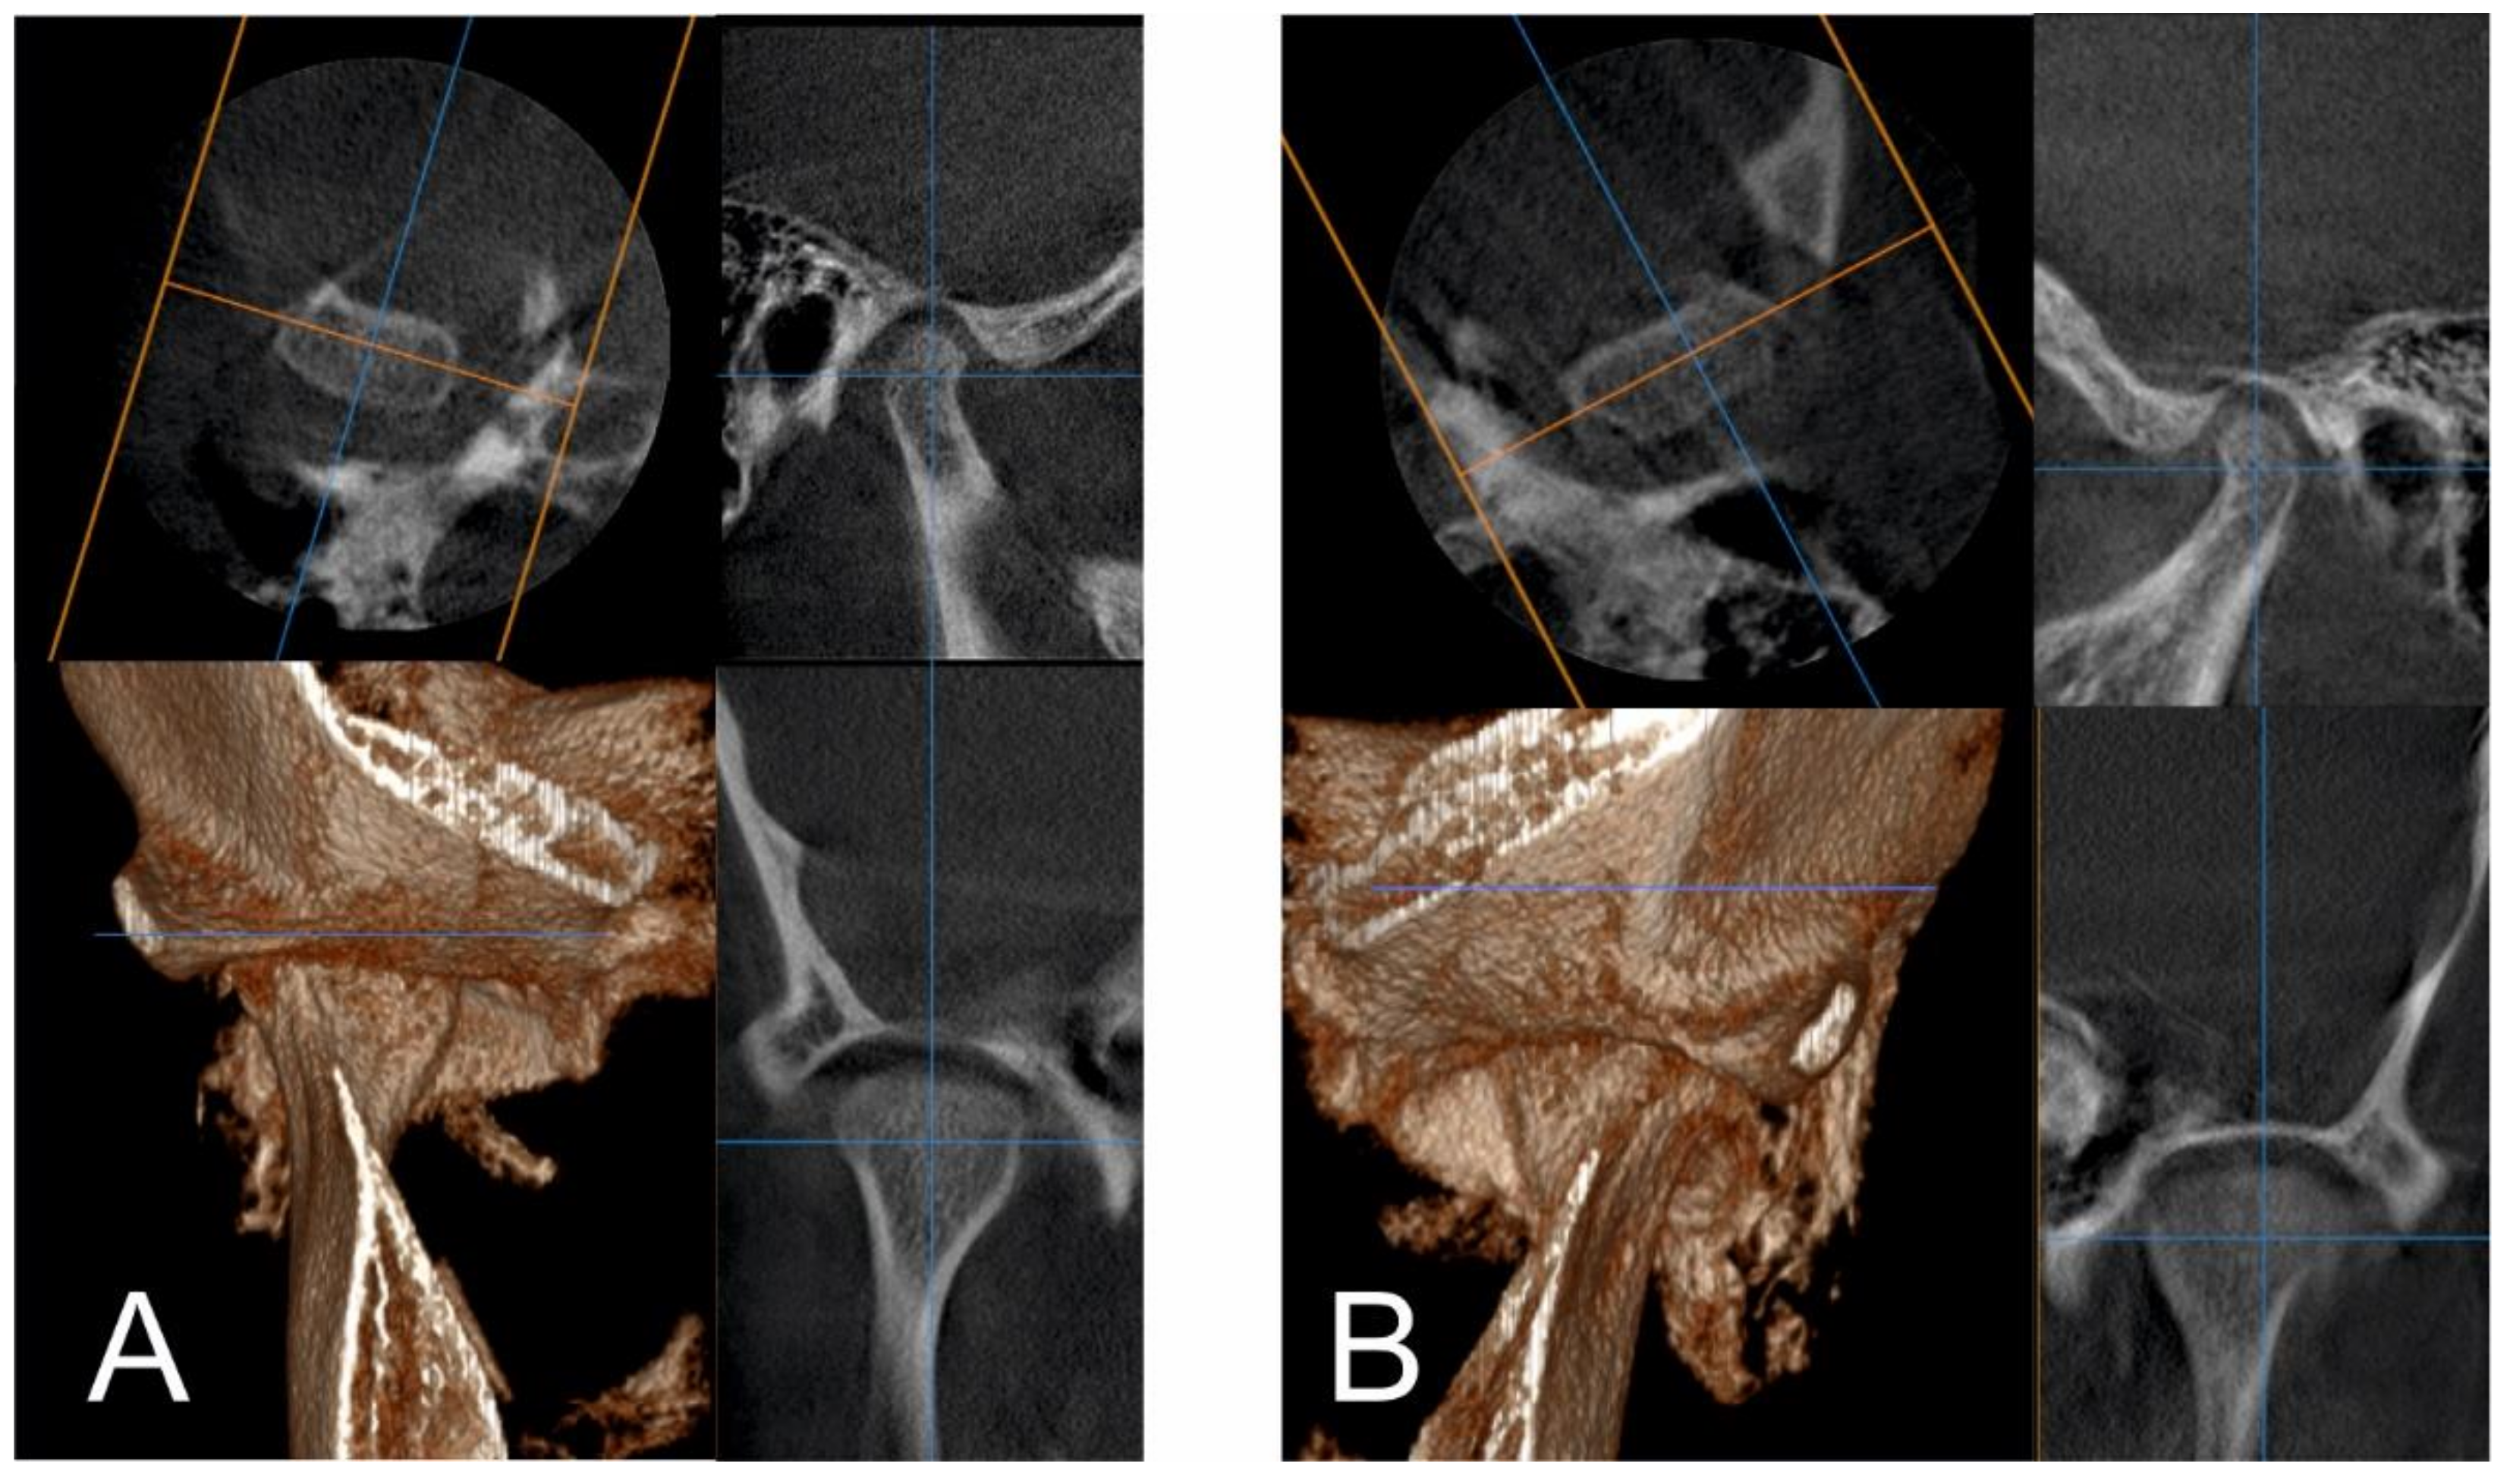

2.1. Initial Diagnosis and Initial Surgical Management

2.3.1. First Treatment Phase—2016—TMJ Splint Therapy

2.3.2. Second Phase of Treatment—2017—Bite-Blocks and Transpalatal Arch